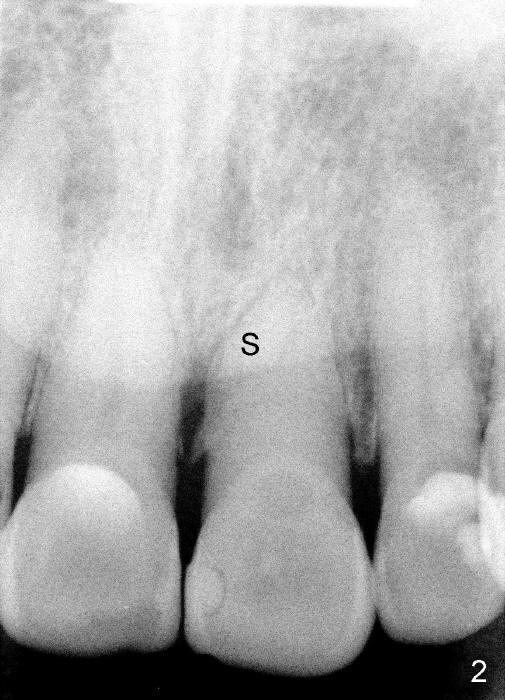

A 65-year-old man had injury to the tooth #9 20 years ago. The tooth has been discolored since (Fig.1). The tooth remained asymptomatic until last year. It has been loose since then. X-ray shows short root (Fig.2 S), sclerosed canal and bone loss mesially. There is a lingual abscess (Fig.8 A) with deep pockets.